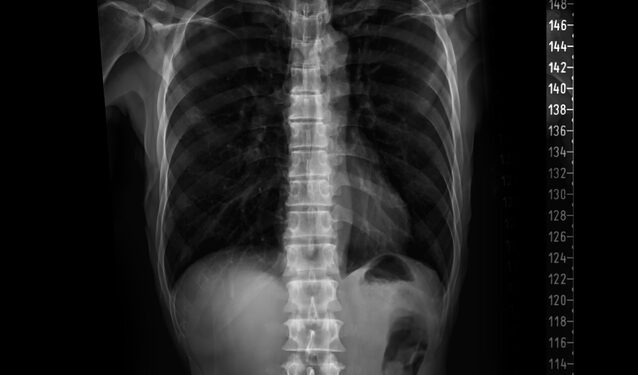

- Pilvo rentgenograma – šis tyrimas padeda pastebėti išsiplėtusias žarnyno kilpas. Jei mekonijus susimaišęs su nurytu oru, nuotraukose gali matytis vadinamų „muilo burbulų“ struktūra.